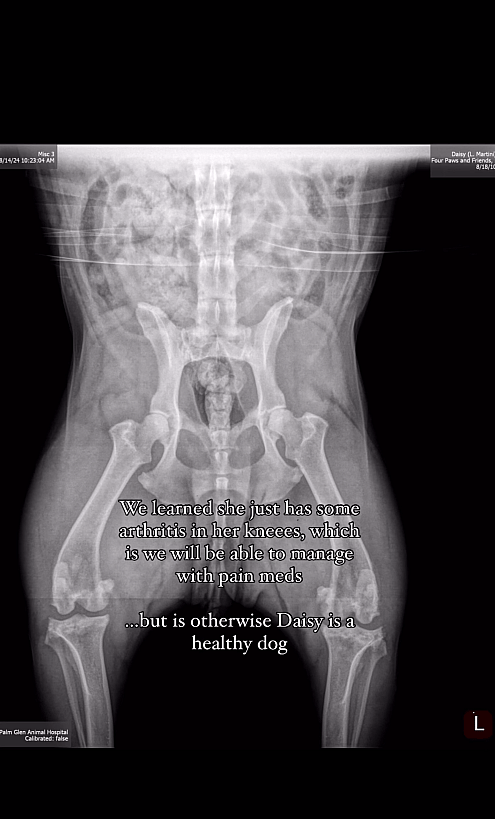

When Daisy arrived at the rescue, the staff noticed a limp in her back left leg. So, they took her to their veterinarian as they were concerned that it was something serious. The tests and X-ray scans revealed that she had arthritis in her knees.

This wasn’t something to be worried about because pain medications would be enough to help the sweet dog. Other than that, Daisy has no other health complications. Overall, she is as healthy and happy as a senior dog could be and this is a testament to how well she is taken care of by her homeless parent.